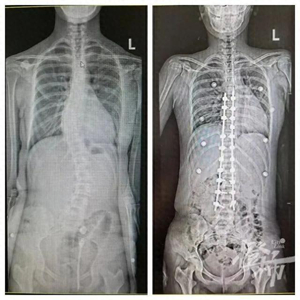

4年前,可可就出现了站立时脊柱歪斜之症,带去当地医院检查,发现是脊柱侧弯,当时配了支具进行保守治疗。后来效果不佳,这次可可父母特意带着孩子来浙大儿院骨科做手术。

没曾想,这次的手术之行还发现了一个大问题,可可的四肢比同龄人要修长得多,且双手下垂甚至能超过膝盖骨科副主任陈文昊当下就怀疑可可极有可能患有马凡综合征。果然,通过基因检测,发现可可确实携带FBN1基因,被确诊为马凡综合征,同时心血管也有问题:主动脉窦增宽、二尖瓣增厚、脱垂伴轻-中度关闭不全

陈主任表示,马凡综合征患儿骨骼发育异常,跟一般的青少年特发性脊柱侧弯以及先天性脊柱畸形又有所不同,给矫正手术增加了一定难度,但好在最后可可的手术结果很不错,达到了预期效果。